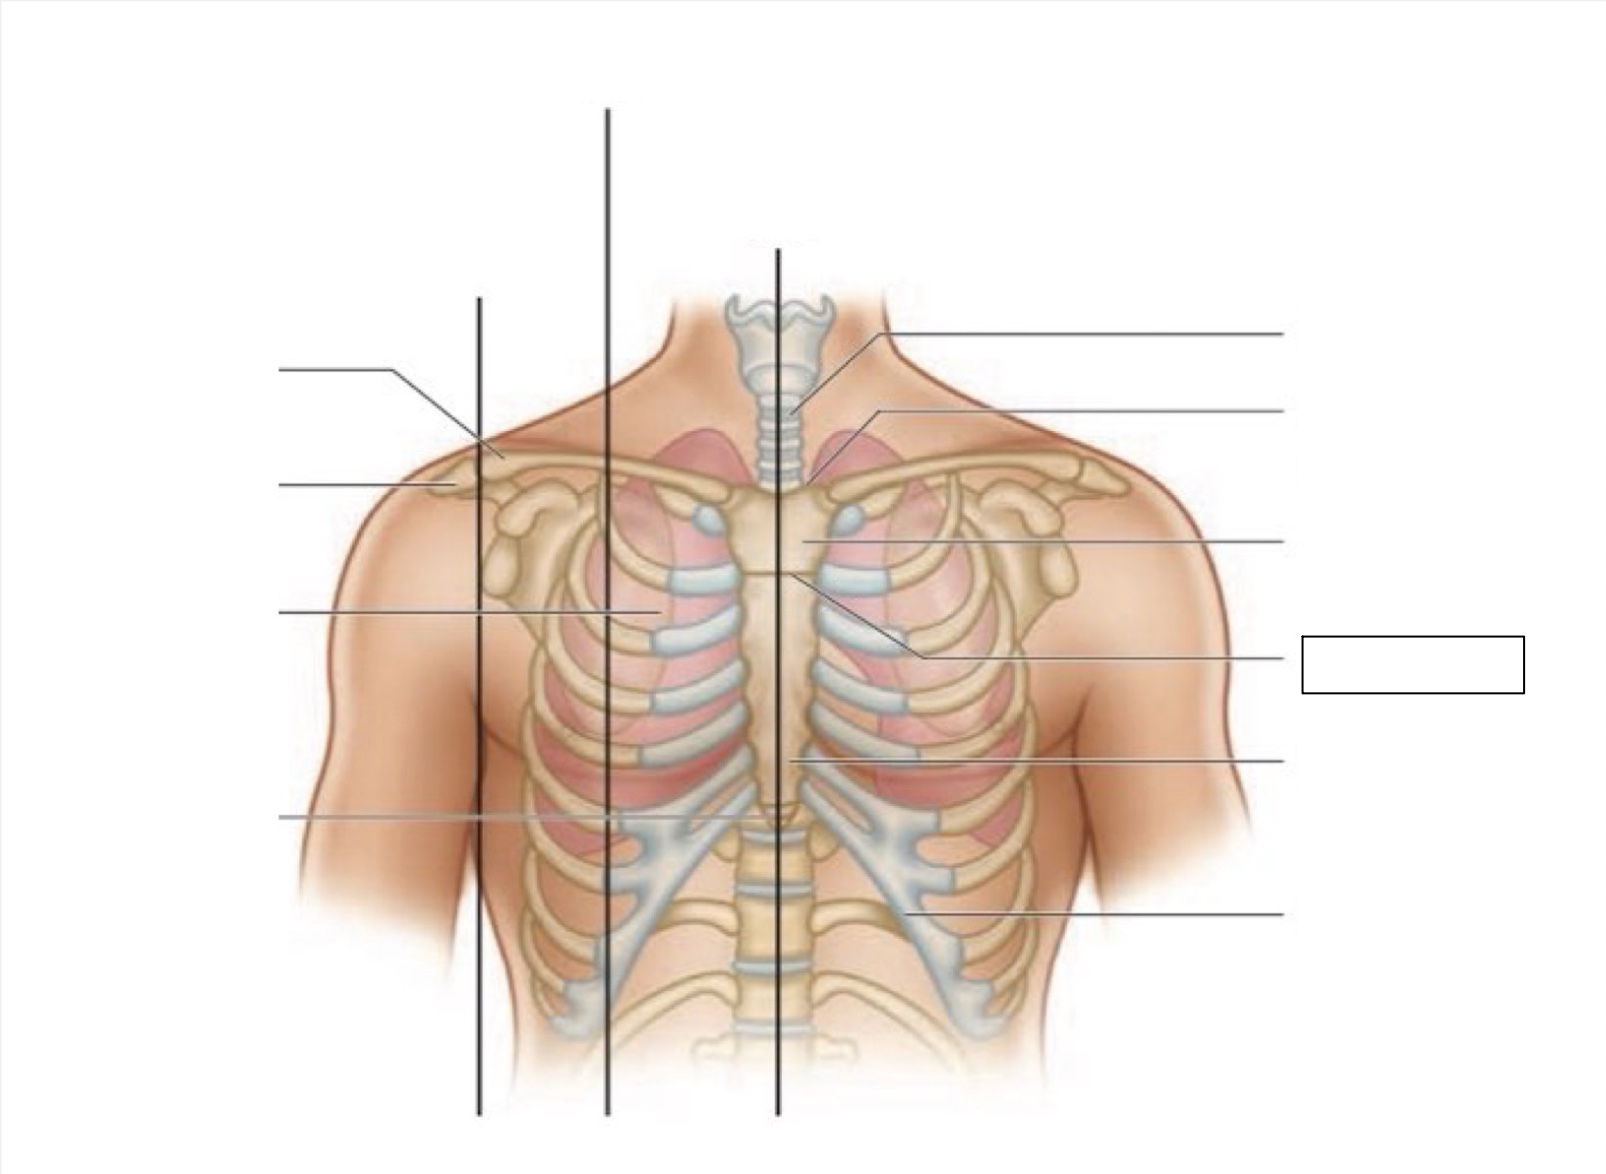

midsternal line

trachea

suprasternal notch

manubrium

angle of Louis

sternum

costal margin

xiphoid process

intercostal space

acromion

clavicle

anterior axillary line

midclavicular line